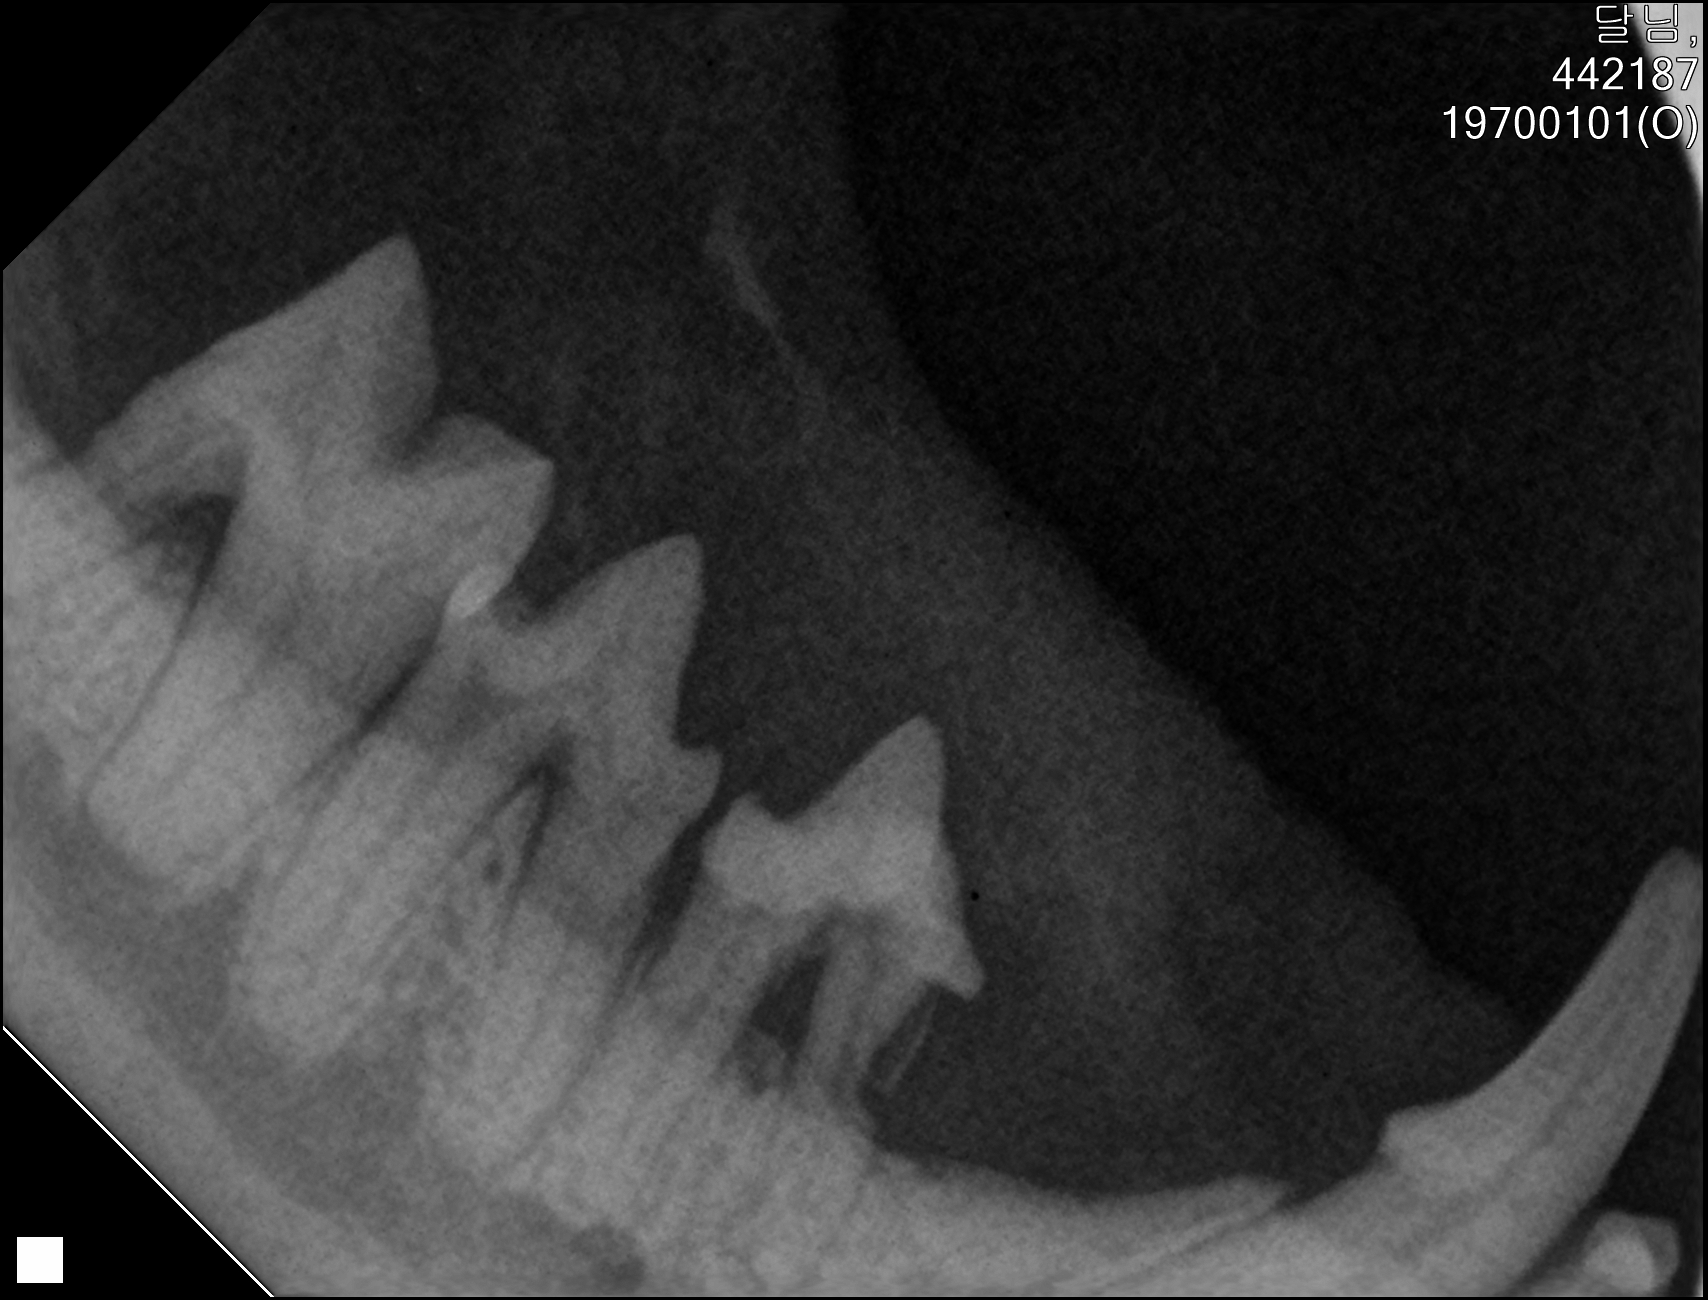

| 치료과정 | 달님이를 병원에 데려갔을때 거의 한달 가까이 먹질 못했기 때문에 몸무게는 2키로 초반대로 나갔고 마취하고 검사할수있는 상태가 아니였기 때문에 피검사를 통해서 간단히 검사후 입원하기 시작했습니다 탈수증세가 너무 심했고 수액을 맞으면서 자발식을 찾으려 했지만 달님이는 전혀 먹질 않았고 입원기간도 길어지게 되었습니다 그 와중에 청천벽력같은 소리를 듣게되었습니다 신장수치가 좋지않아 신부전이라는 결과였습니다 손도안타는 이아이를 제가 과연 케어할수있을까 너무 너무 걱정이였고 눈물이 앞을 가렸습니다 하지만 우선 체력을 회복한후 걱정은 나중에 하기로하고 달님이 치료에 집중하기 시작했습니다 병원에서도 선생님들이 달님이를 강제 급여도 해주고 수액도 계속 맞고 보니 꽉 막혀있던 코에서 콧물도 나고 소변도 보기 시작했습니다 그리고 다시 검사를 하고나니 다행히 신부전은 아니고 지방간이라고 하였습니다 아마도 오래전부터 먹는양이 줄어들었고 최근에 들어 아예 먹질못해서 간이 망가졌고 황달증세가 생겼다고합니다 어떤 이유에서인지모르겠지만 달님이는 원래 호흡기도 안좋았고 항상 콧물과 재채기를 달고산 아이라 호흡기도 안좋았고 이빨상태도 안좋아 밥을 못먹기 시작했던거같습니다 우선 체력회복이 중요하기때문에 집에서 케어한후 간 회복후 추후에 발치를 하기로 하였습니다 집에 온후 달님이는 바로 사료를 먹기시작했습니다 아마도 병원이 싫어서 밥을 안먹었던 모양입니다 매일 처방식과 약을 먹이면서 살을 찌우기 위해 이것저것 달님이가 좋아하는 캔과 츄르를 바치기 시작했고 다행히 달님이는 매일 맛있는 밥을 먹으며 살이 찌기시작했습니다 한달되는 날 발치와 검사를 위해 병원에 가서 검사를 하였는데 달님이는 3.86키로로 몸무게도 상당히 늘었으며 검사결과 모든 수치가 좋아졌습니다 그리고 마취후 이빨상태를 보니 치주염이 심각했고 이빨은 어금니부터 송곳니까지 다 내려앉은 상태였습니다 입안은 구내염이 시작되었고 원장님은 송곳니도 지금도 안좋지만 나중에 되면 더 아퍼질꺼라며 전발치를 해야한다 하였고 저는 달님이과 전발치를하고 길에서 잘 살수있을까 너무 걱정이였지만 나중에 아파서 또 구조후 마취하는것보다 낫다고 생각했고 밥자리도 잘 되어있어 전발치하고도 잘사는길냥이들 많다고 들어서 전발치를하게되었습니다 달님이는 수술을 잘 마쳤고 퇴원후 달님이는 집에서 10일정도는 약먹고 회복해야하기때문에 집에서 좀더 케어한후 방사할 예정입니다 |